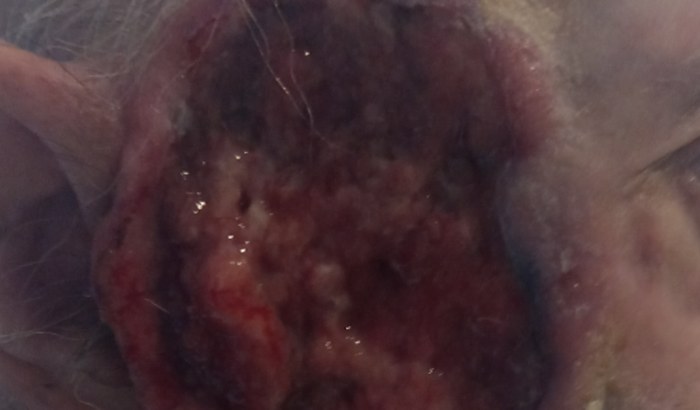

Câncer de Pele.

Me chamo Leidiane dos Santos Silva e estou criando essa vaquinha online para ajudar um amigo, pai e muito mais. Ele se chama Francisco Regis de Azevedo Tornaghi. Foi e ainda é uma pessoa que ajuda muitas pessoas e hoje ele está passando por uma fase muito difícil da sua vida. Agora ele está precisando muito da ajuda dos amigos para que ele possa realizar um tratamento de câncer de pele, o qual vem lutando desde o ano passado. Esse ano o câncer voltou e está progredindo de forma muito agressiva. Ele está sendo acompanhado pelo SUS mas o SisReg não dá conta de atender de imediato. Terá que fazer exames muito caros como: análise imunohistoquimico de origem tumoral, tomografia de face, pescoço e tórax. Hoje ele mora em Pedra de Guaratiba e está sendo acompanhado no Hospital MÁRIO KROEFF, na penha, muito longe de casa e fica difícil para a locomoção. Quando começar radioterapia e quimioterapia terá que ir todos os dias. Precisará fazer radioterapia todos os dias e quimioterapia 2 vezes na semana. Para ir de transporte público tem que pegar 4 conduções. Ele não aguenta pois tem 75 anos de idade.Por esse motivo estou aqui fazendo essa vaquinha para que os amigos e familiares possam colaborar com qualquer quantia para ajudar nesse momento muito difícil. Desde já agradeço a todos pela ajuda.